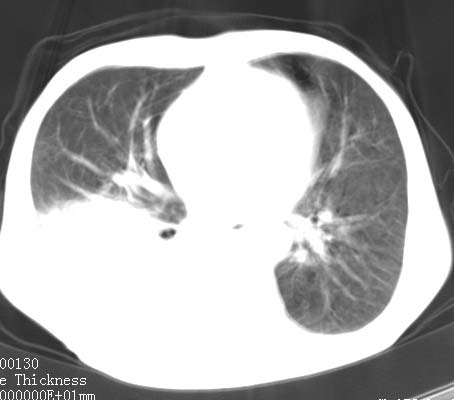

病人女 60岁 咳嗽 气促十余天,大叶性肺炎.

右肺上下叶均见 大片状密度增高影,边界清晰,其内可见支气管充气征,气管支气管通畅。纵膈略向右移位,其内无肿大淋巴结影。首先考虑炎性病变。不排除一些特异性的炎症。不知道发烧吗??wbc高吗??建议治疗后复查!!

看影响还是首先考虑炎性改变,建议实验室检查,还有要警惕炎性肺泡癌,具有的枯枝征象。

右肺感染性病变(大叶性肺炎可能);建议抗炎治疗后复查。

看影像还是首先考虑炎性改变,建议实验室检查,还有要警惕炎性肺泡癌,具有的枯枝征象